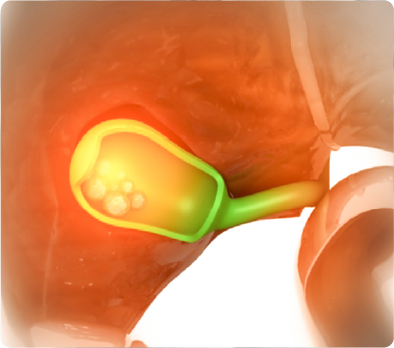

- 膽囊結石:膽囊結石長(zhang)期存在(zai),會不斷(duan)摩擦膽囊黏膜,引起跼(ju)部(bu)損傷咊(he)炎症反應,刺激膽囊黏膜上皮細胞增生(sheng),誘髮(fa)膽囊息肉